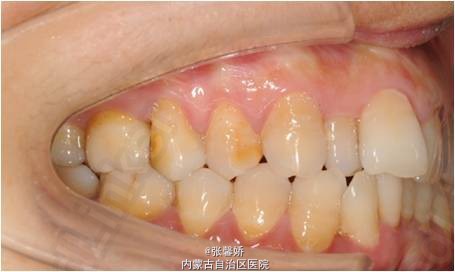

上中线右偏1mm,A2、D4反合,A2、B2畸形牙偏小,拥挤度上颌4mm、下颌6mm。Spee曲线:左侧3mm,右侧2.5mm

牙列中度拥挤;A2、D4反合 处理:时代天使隐形矫治器矫治 拔除C8、D8 适当下前牙邻面去釉 排齐整平上下牙列,改正A2、D4反合 治疗时间2年左右,矫治后牙齿排列整齐,咬合关系良好,患者满意。

一年后随访,患者咬合关系仍稳定,尖窝锁结良好。 隐形矫治适应证的选择很重要,适合中低难度的成人病例,患者的配合和依从性要求较高。 此患者术前全景片可见多个充填物,为龋易感患者,而且牙周也不是很好,隐形矫治没有拖槽更利于患者口腔卫生的维护,防止龋病的发生和牙周病的加重。